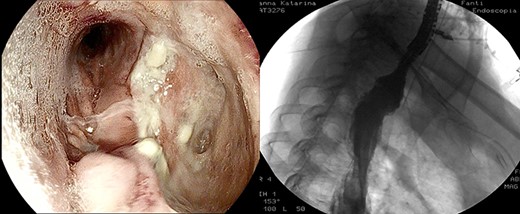

Healthy-appearing granulation tissue and progressive reduction of leak and cavity size.

The patient underwent 14 treatment sessions over 35 days. The leak and the cavity size progressively improved with the development of healthy-appearing granulation tissue s (Fig. 3). Inflammatory indexes and clinical conditions similarly improved. The endoscopic findings were confirmed by CT scans. Complications were not observed.